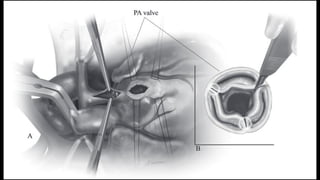

Exposure of ventricular septal defect

and right ventricular outflow tract

through tricuspid valve. B:

Infundibular resection is complete

and pulmonic valve can be seen.